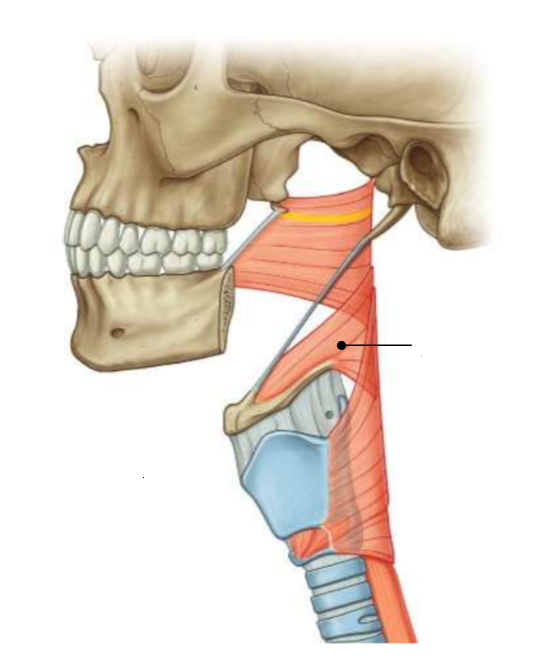

What is this muscle?

middle constrictor

What are the attachments of this muscle?

lower stylohyoid ligament, lesser and greater horns of hyoid → pharyngeal raphe

What muscle is this?

inferior constrictor

Which part of the muscle is 1?

thyropharyngeus

Which part of the muscle is 2?

cricopharyngeus

What are the attachments of this muscle?

oblique line of thyroid cartilage, cricothyroid tendon, cricoid cartilage → pharyngeal raphe